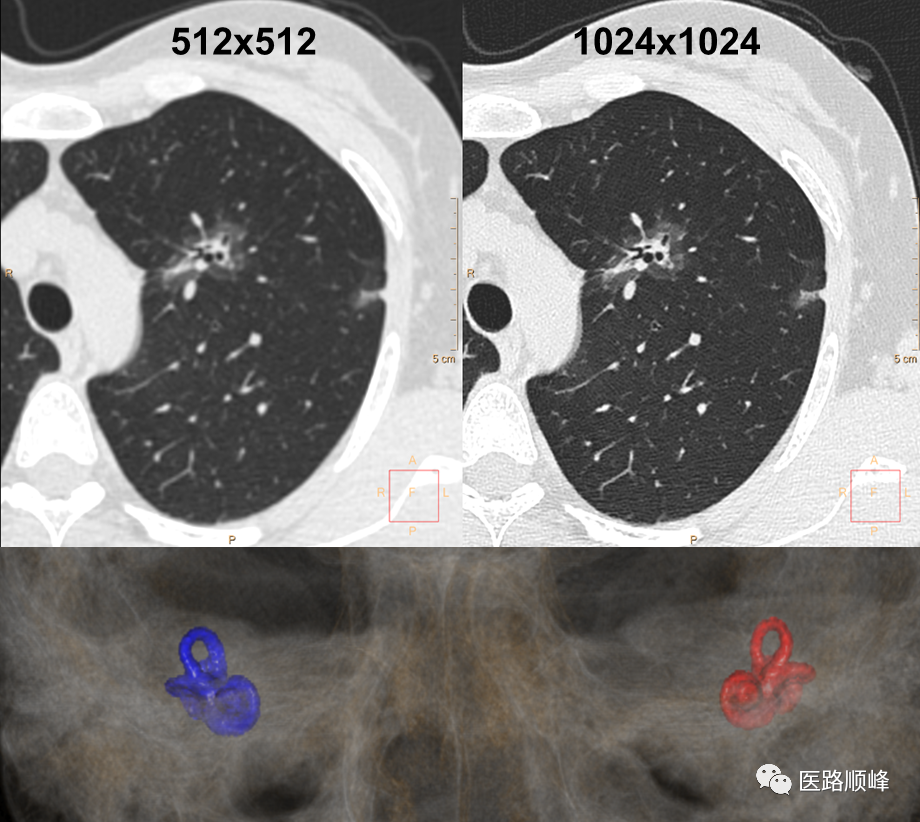

• 1024超高清成像

满足各种细节诊断需求,包括但不限于肺结节高清靶扫描成像、听骨链重建、全身血管CTA成像。

ct为什么需要预热机器Computed Tomography专栏:Incisive CT 球管预热_https://www.jmylbn.com_新闻资讯_第19张

• 70kV低剂量检查

真正临床化的低剂量扫描,可应用于临床各部位检查,包括但不限于低剂量体检、低对比剂血管造影检查等。

ct为什么需要预热机器Computed Tomography专栏:Incisive CT 球管预热_https://www.jmylbn.com_新闻资讯_第20张